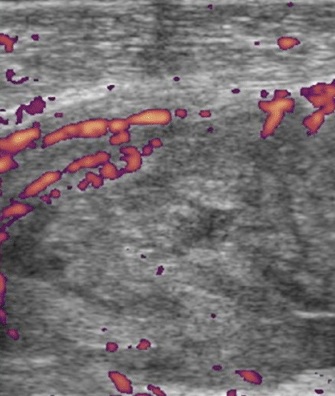

Znacznego stopnia przerost błony maziowej w zachyłku nadrzepkowym z widocznymi wzmożonymi echami przepływów w badaniu Power Doppler – aktywny proces zapalny w przebiegu RZS.

W konsekwencji prowadzi to do trwałych zwyrodnień i zniekształceń stawów. Badanie USG wykorzystywane jest coraz częściej w diagnostyce RZS, gdyż dostarcza informacji na długo wcześniej od objawów prezentowanych na klasycznym zdjęciu rentgenowskim i badaniu tomograficznym. Dzięki głowicom o wysokiej częstotliwości, badanie USG pozwala na jakościową ocenę przerostu błony maziowej wraz z oszacowaniem jej aktywności zapalnej w badaniach dopplerowskich oraz dokładne obejrzenie powierzchni stawowych pod kątem wykrycia nadżerek. W przypadku pacjentów ze stwierdzonym i leczonym RZS należy podkreślić nieocenioną rolę badania USG z funkcją dopplerowską. Pozwala ona bowiem potwierdzić lub ocenić stopień aktywności choroby, ale także wcześnie wykazać zaostrzenie choroby, jeszcze zanim dojdzie do pojawienia się typowych, klinicznych objawów zaostrzenia.